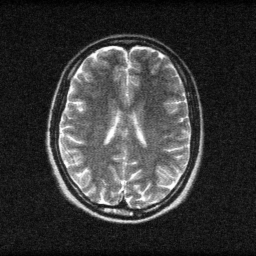

Method: CPU_baseline | Mismatch: nominal (nominal=True, perturbed=False)

Ground Truth

Measurement

Reconstruction